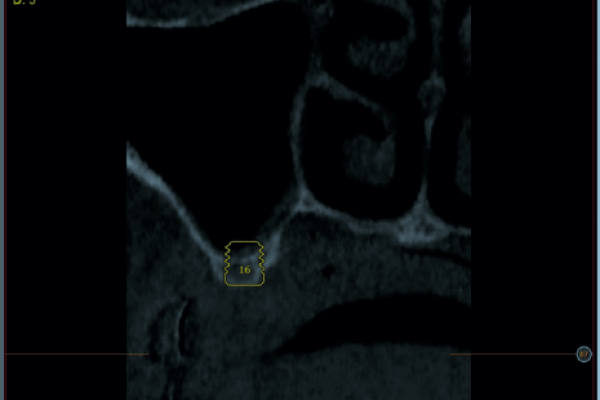

Relación entre los anticonceptivos orales y la incidencia de alveolitis. Revisión bibliográfica